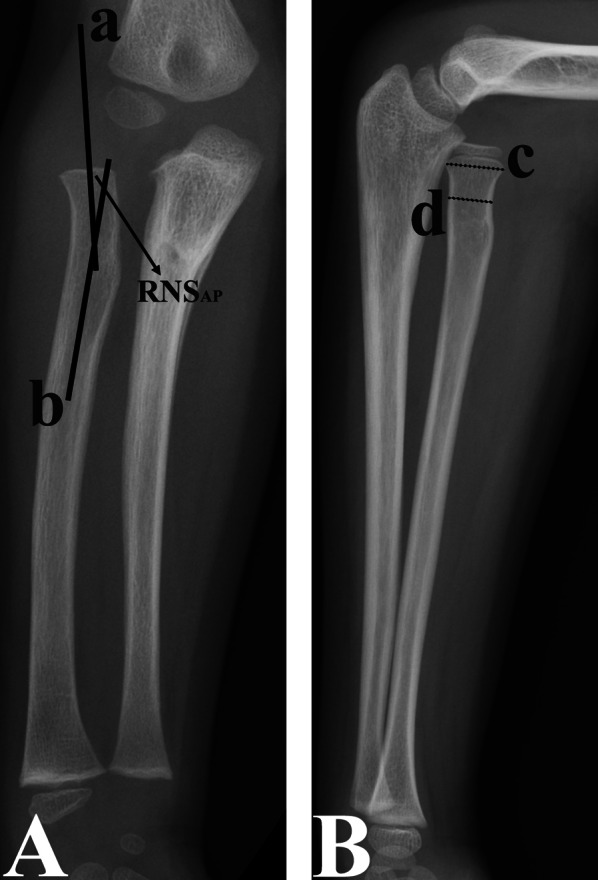

Materials and methods: The clinical data of 142 patients (mean age at the time of injury: 5.73 years) with untreated unilateral CMFs were retrospectively reviewed. The radial neck-shaft angle (RNSAP) and radial head size (RHL) were measured on anteroposterior (AP) and lateral (L) radiographs, respectively. The RHL size was the ratio of the widest width of the proximal radial metaphysis to the narrowest radial neck width. The En-RNSAP and En-RHL were the ratios of the enlargement (En) of the RNSAP angle and RHL size of the injured elbow to those of the uninjured elbow, respectively. Paired-sample t-tests, single-factor analyses and multiple linear regression analyses were performed to evaluate the correlation between the differences in these parameters between the injured and uninjured elbows and the assessed risk factors. These risk factors included institution, sex, laterality, age at injury, time from injury to diagnosis, direction of RH dislocation, distance of RH dislocation (DD-RH), presence of radial or median nerve injury, heterotopic ossification and immobilization of the elbow after injury.